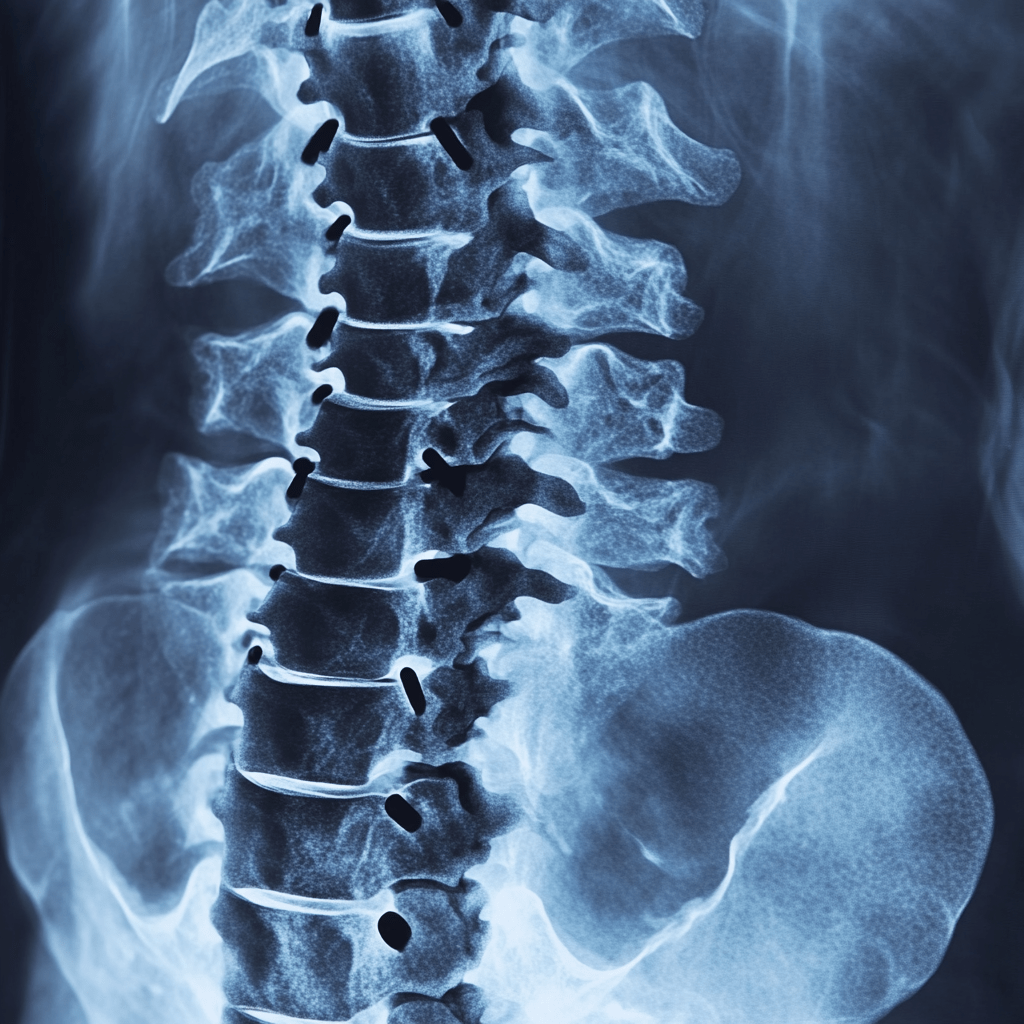

Tratamientos Avanzados para la Columna Vertebral

El dolor crónico de columna es la principal causa de incapacidad en el país.

Este padecimiento requiere de un tratamiento específico y adecuado para cada caso.

Cuidado con bajo riesgo de complicaciones y reincidencia.